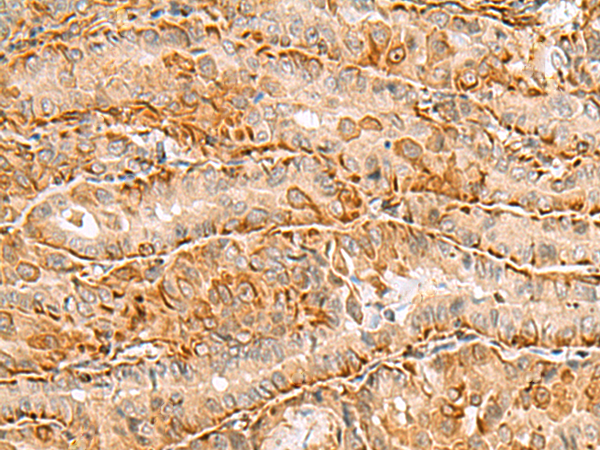

分类: 科研抗体货号: P09413别名:应用: IHC反应种属: Human, Mouse, Rat